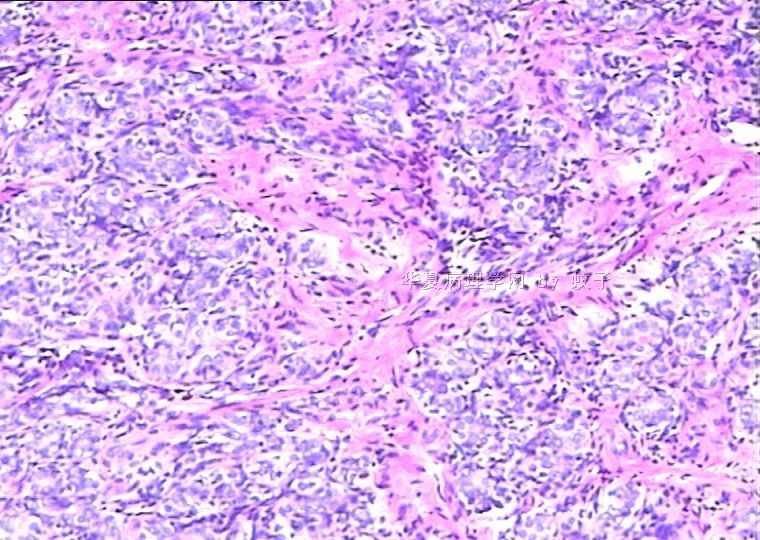

B2156乳腺活检

姓    名: ××× 性别:  女 年龄:  20

简要病史:  右乳包块8年。

肉眼检查:  灰白不整形组织一块,切面灰白,灰红,实性,质韧。

• 乳腺活检图2

图2

标签:乳腺腺病

旺识型腺病

有包膜吗?良性,首先考虑纤维腺瘤(图5、6透明变的纤维支持),其次腺瘤。

无明显包膜,界限较清,

我们考虑腺瘤,(图5,6为混有纤维瘤组织)

腺病瘤(主要成份旺炽性腺病)部分区域为纤维腺瘤(管内型)